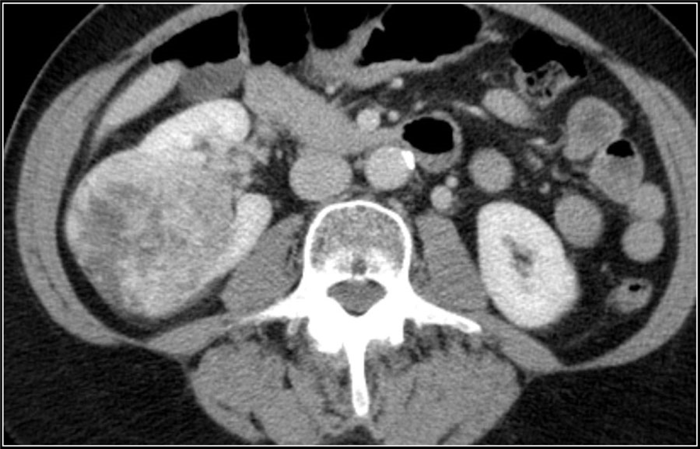

(Справа) КТ с контрастированием, аксиальная проекция: у мужчины 47 лет с остро возникшей болью в правом боку после мотоциклетной аварии выявлен травматический инфаркт правой почки вследствие тупой травмы. (Слева) КТ с контрастированием, аксиальная проекция: у мужчины 38 лет, получившего тупую травму из-за автокатастрофы, выявлен обширный инфаркт почки с отсутствием контрастирования. Обратите внимание на слабое контрастирование кортикального ободка.

(Справа) КТ с контрастированием, аксиальная проекция: у этого же пациента обнаружена только небольшая контрастируемая область левой почки. Выявлен тромбоз левой почечной артерии в результате травматического расслоения.